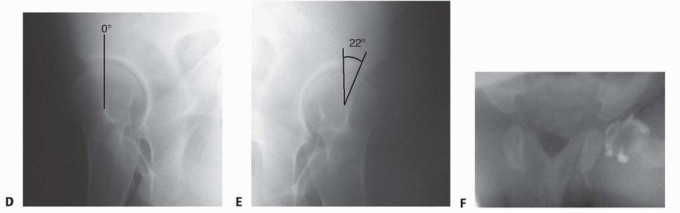

FIG 4 • A. Coronal section ultrasound imaging through the most posterior aspect of the acetabulum. The femoral head is well visualized dislocated from the acetabulum. B. Seven-month-old child with a dislocated left hip. The acetabulum is steep. The femoral ossific nucleus is not present. There is a break in the Shenton line on the left and it is normal on the right. C-E. Radiographs of young adult with high-grade right acetabular dysplasia. C. On the AP pelvic view, the center-edge angle (CEA) on the left is low normal (26 degrees); on the right, it is 10 degrees. The Shenton line is intact, indicating that there is no subluxation. D,E. Right hip false-profile views.

Right hip CEA is 0 degrees and left hip CEA is 22 degrees.

IMAGING AND OTHER DIAGNOSTIC STUDIES

Ultrasound is a useful imaging method up to 6 months of age (

FIG 4A

).

The two most common indications for ultrasound imaging are for screening the asymptomatic infant considered to be at high risk for hip dislocation (girls born breech have a 133/1000 risk of DDH) and for following an infant with proven DDH, especially during Pavlik harness treatment.

The AP radiograph is most useful in infants older than 6 months of age.

In children older than 3 years of age, the Shenton line is a reliable indicator of subluxation (

FIG 4B

). The Von Rosen view in abduction and internal rotation shows the ability of the femoral head to reduce.

In the adolescent or adult hip, a standing AP pelvis view is obtained with measurement of the center-edge angle, as well as standing false-profile views of each hip joint (

FIG 4C-E

The normal center-edge angle on the AP pelvic radiograph is greater than 24 degrees.

Intraoperative arthrography can show whether the femoral head is fully reducible with no medial pooling of contrast (

FIG 4F